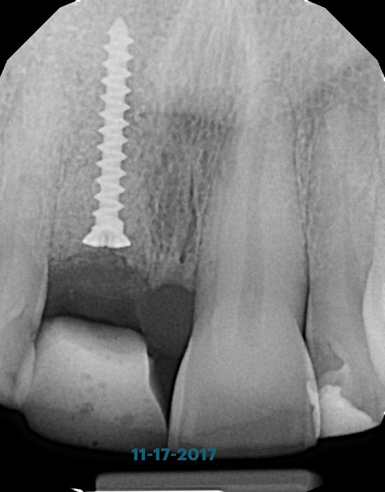

(6.) Pretreatment periapical radiograph.

Figure 6

A 56-year-old female patient was referred for the evaluation of tooth No. 8 (Figure 4 and Figure 5). A periapical radiograph indicated that the tooth had undergone apicoectomy and received an excessively long post (Figure 6), and a cone-beam computed tomography (CBCT) scan of the site revealed a lack of buccal plate bone (Figure 7).